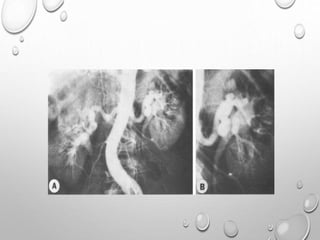

DYSPLASIA EPIPHYSEALIS

HEMILELIA

TREVOR DIASEASE

NON GENETIC

ASSOCIATED WITH SCLEROSING SKELETAL DYSPLASIA , BENIGN

CARTILAGINOUS LESIONS

THREE CATEGORIES : MONOSTOTIC

CLASSICAL FORM – MORE THAN ON BONE IN

SINGLE LIMB

GENERALZSED OR SEVERE FORM – ENTIRE LIMB

CLINICAL FEATURES

PRESENTING DURING IST DECADE

SYMPTOMATIC WHEN ASYMMETRICAL EPIPHYSEAL GROWTH

INTERFERE NORMAL RANGE OF JOINT MOTION

LIMB SHORTENING , OR LENGTHENING

HARD BONY SWELLING

REGIONAL MUSCULAR ATROPHY , CLUMSY GAIT

PREDOMINANTLY LOWER LIMB

MONOMELIC

MEDIAL > LATERAL

MOST COMMON SITES : DISTAL FEMUR ,

DISTAL TIBIA AND TALUS

SMALL BONES OF HAND AND FEET CAN

ALSO BE INVOLVED

ASYMMETRICAL LOBULATED

OVERGROWTH OF EPIPHYSES WHICH

IS DESCRIBED AS

OSTEOCARTILAGINOUS TUMOR

HISTOLOGICALLY.SOMETIMES

COMPOSED OF MULTIPLE

OSSIFICATION CENTERS , MAY REMAIN

SEPARATED FROM THE EPIPHYSES

RADIOGRAPHS USUALLY DEMONSTRATE A PARTIALLY OSSIFIED, LOBULATED,

CARTILAGINOUS MASS ARISING UNILATERALLY FROM THE AFFECTED

EPIPHYSIS WITH OR WITHOUT AN OSSEOUS CONNECTION. THE DIAGNOSIS

IS USUALLY MADE WITH RADIOGRAPHS, BUT THE LESION CAN BE MISTAKEN

FOR AN INTRA-ARTICULAR LOOSE BODY, OSTEOCHONDROMATOSIS, OR

SYNOVIAL CHONDROMATOSIS.

CT CAN HELP DEFINE THE ANATOMIC RELATIONSHIP BETWEEN THE MASS AND

THE HOST BONE, AND MRI CAN SHOW THE EXTENT OF EPIPHYSEAL

INVOLVEMENT AND JOINT DEFORMITY AND THE STATUS OF THE ARTICULAR

SURFACE.

THERE MAY BE A CLEAVAGE PLANE DEMONSTRATED BETWEEN THE LESION

AND HOST BONE THAT GRADUALLY OSSIFIES AS THE LESION MATURES

CORONAL COMPUTED TOMOGRAPHY SCAN OF THE ANKLE

DEMONSTRATING IRREGULARLY SHAPED PROTUBERANT BONE

(WHITE ARROW) IN THE MEDIAL ASPECT OF THE JOINT (A). AXIAL

COMPUTED TOMOGRAPHY SCAN OF THE ANKLE DEMONSTRATING

AN IRREGULARLY SHAPED PROTUBERANT BONE LESION OF THE

MEDIAL ANKLE JOINT, WITH A PORTION CONNECTED TO THE

ANTERIOR TALUS, AND A SECOND LESION MORE POSTERIORLY

LOCATED AND A DEFINED CLEFT (BLACK ARROWS) AT THE

INTERFACE (B).